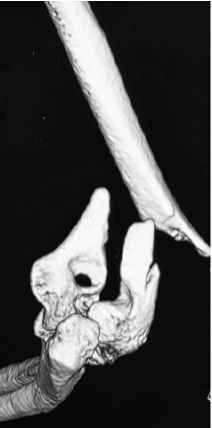

Outcomes of Internal Fixation in Proximal Humerus Head Split Fractures in Young Adults – How Often Is It Missed and Can We Really Afford to Do So

Kaustav Mukherjee , Tarun Prashanth , Dorai Kumar Raja , Mohan Kumar